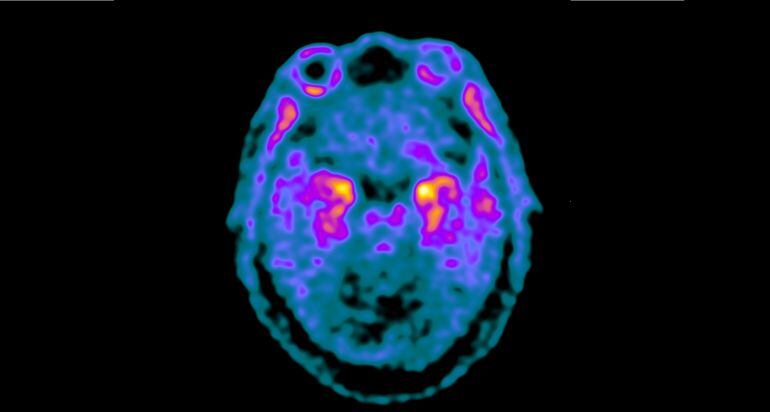

Imatge de PET-Tau en un pacient amb Alzheimer / Servei de Medicina Nuclear (Hospital de la Santa Creu i Sant Pau)

En l’estudi s’administra en els pacients un traçador radioactiu PET que detecta la proteïna tau i els seus cúmuls anormals en el cervell dels pacients. L’estudi està finançat per la Fundación BBVA i l’Instituto de Salud Carlos III.

Tant la demència frontotemporal com la malaltia d'Alzheimer comparteixen acumulacions anormals de proteïna tau en l’interior de les neurones, cosa que provoca la mort d’aquestes cèl·lules.